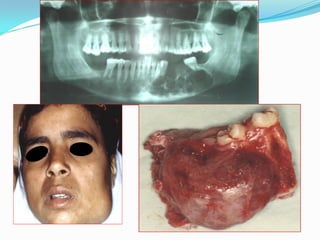

Ameloblastoma

 The ameloblastoma is the most common odontogenic tumor. It is a

benign but locally invasive neoplasm derived from odontogenic

epithelium tumor arising from the dental lamina, Hertwig sheath, the

enamel organ, or the lining of dental follicles/dentigerous cysts . It has

three different clinico-pathologic subtypes:

 Multicystic , solid (86%),

 Unicystic (13%) and

 Peripheral (extraosseus – 1%).

 It usually occurs in the 4th and 5th decades without a gender

predilection.

 It is typically slow-growing, locally invasive and

runs a benign course.

 WHO described it as being a benign tumor that

is “usually unicentric,(unilocular) non-functional,

intermittent in growth, anatomically benign and

clinically persistent.”

 It may develop from cell rests of the enamel

organ; from the developing enamel organ; from

the lining of odontogenic cysts or from the basal

cells of the oral mucosa.

 It may arise from the lining of a

dentigerous cyst but more often

arises independently of

impacted teeth. It is

characterized by a progressive

growth rate and , when

untreated, may reach enormous

proportions.

 Early symptoms are often

absent, but late symptoms may

include a painless swelling,

loose teeth, malocclusion, or

nasal obstruction

Radiographic findings

 Radiographs classically show a well-circumscribed,



expansile soap-bubble radiolucency with clearly

demarcated borders.

However, the unilocular lesion is indistinguishable from

an odontogenic cyst. The extent of root resorption may

indicate a neoplastic process.

Well-circumscribed, soap-bubble

Unilocular – often confused with odontogenic cysts

Root resorption – associated with malignancy